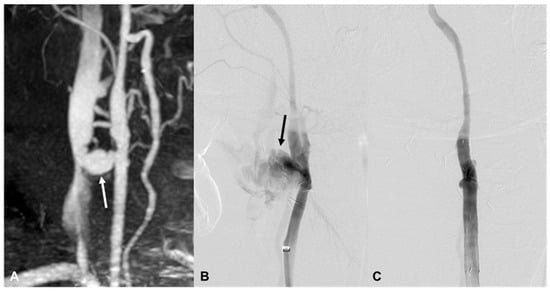

| 2 | 80/F | Fall | Neck swelling | PA, R posterior thyroid | PA, R VA (V2) | bStent | Stable 717 d F/U |

| 10 | 25/M | Blunt | Ear bleeding | Hematoma, retropharyngeal space | EV, L VA (V2) | bStent, coil | Brain death 12 d |